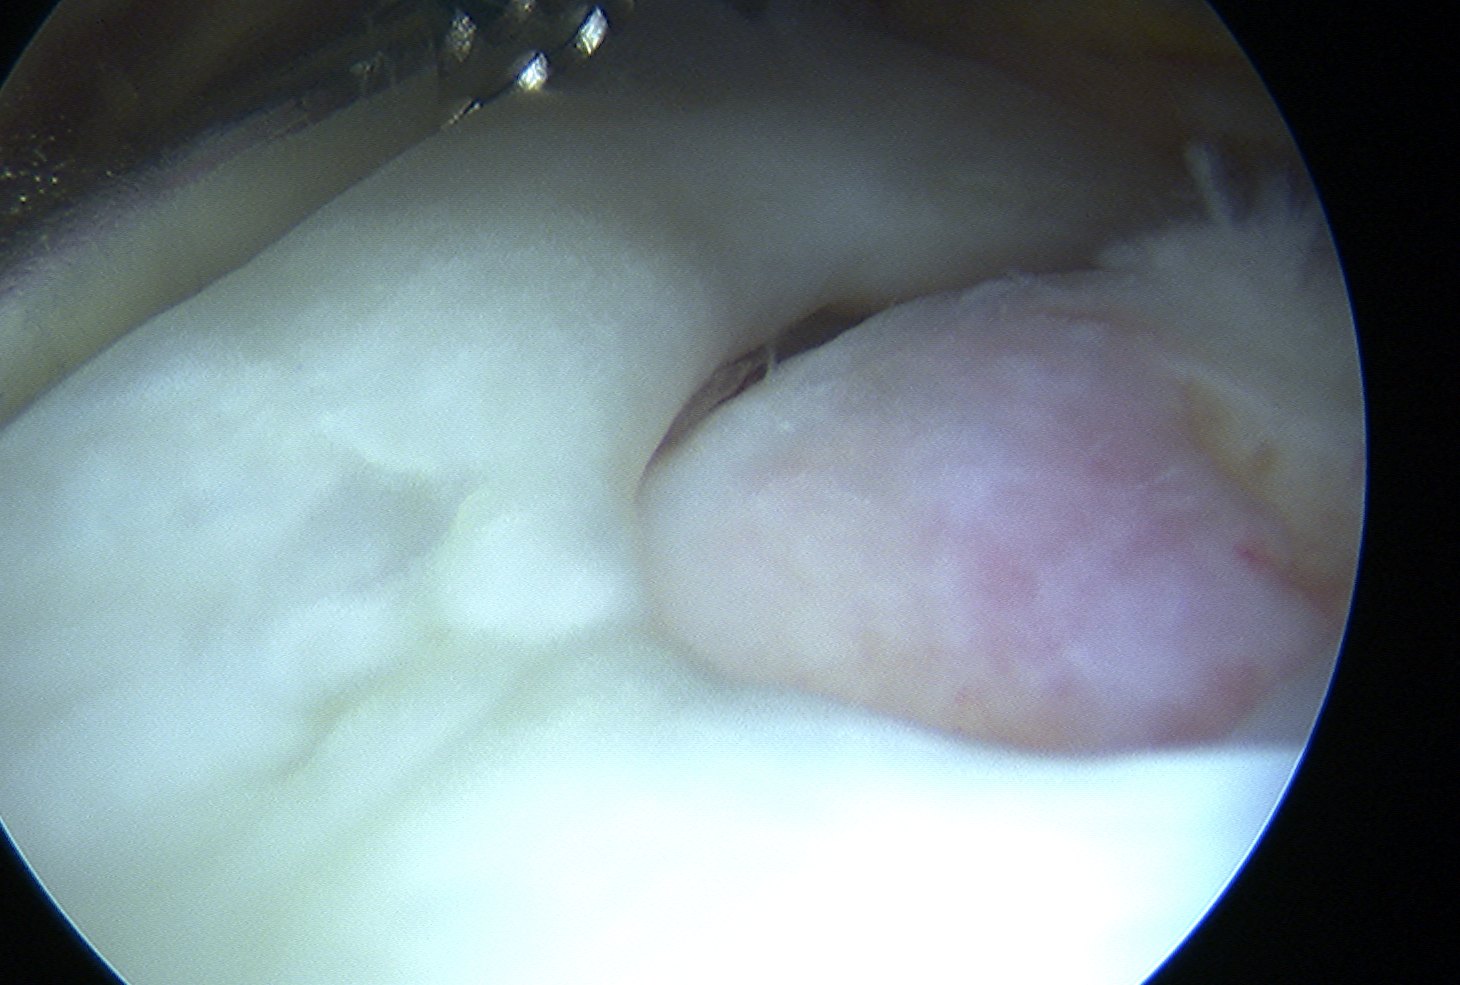

Glenohumeral joint

- inspect subscapularis

- evaluate SLAP / LHB tendinosis - tenotomy / tenodesis

Subacromial joint

- bursectomy for visualization

Assess tear